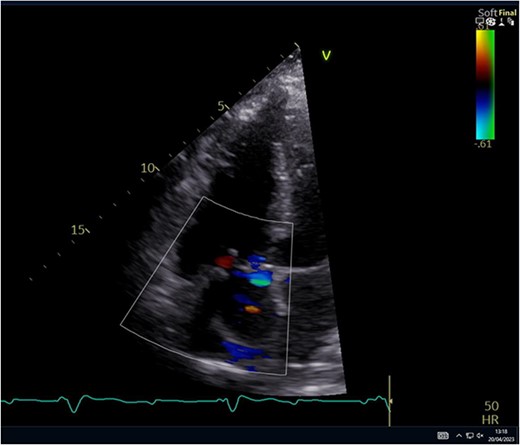

A 29-year-old man with a history of ventricular septal defect closure as a child, presented with severe multi-organ injuries after being run down by two cars. He was intubated on the scene by the hospital emergency medical services before being taken to the emergency department for haemodynamic stabilization and multiple imaging procedures. He suffered extensive bilateral degloving scalp lacerations and a haematoma due to bleeding from his left temporal artery. Computed tomography scan revealed bilateral multilevel rib fractures, a left-sided flail segment, bilateral haemopneumothoraces, and multifocal lung contusions, for which bilateral intercostal chest drains were inserted. Moreover, he had a shallow pneumopericardium, a subcapsular left renal haematoma, an extraperitoneal pelvic hematoma, displaced right-sided superior and inferior pubic ramus fractures as well as slight diastasis of the left sacroiliac joint. Although maximum resuscitation measures were taken with adequate fluid and blood product resuscitation, he remained persistently hypotensive and had worsening haemodynamics despite maximal inotropic support. A transoesophageal echocardiogram demonstrated a flail anterior leaflet of the TV and ruptured papillary muscle head (Fig. 1) with torrential tricuspid regurgitation (TR) and high right atrial (RA) pressures (Fig. 2).